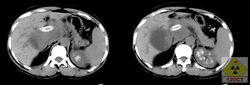

腎自截 腎自截為腎結核終末期病變,是泌尿繫結核的一種特殊病理類型,發生於極少數病人,此時輸尿管因結核侵蝕,完全阻塞,全腎在腎積水或積膿基礎上廣泛鈣化,混有乾酪樣物質,結核桿菌不能隨尿液流入膀胱,膀胱的繼髮結核病變反而好轉和癒合,症狀消失。腹部平片顯示病變腎不同程度鈣化,IVP檢查病變腎無造影劑充填,同側輸尿管未顯示。CT在平腎門水平可見花瓣狀或彎曲充盈腸腔樣鈣化,為CT診斷腎自截的典型特徵,可與腎腫瘤、腎囊腫及腎膿腫等引起的鈣化相鑑別。